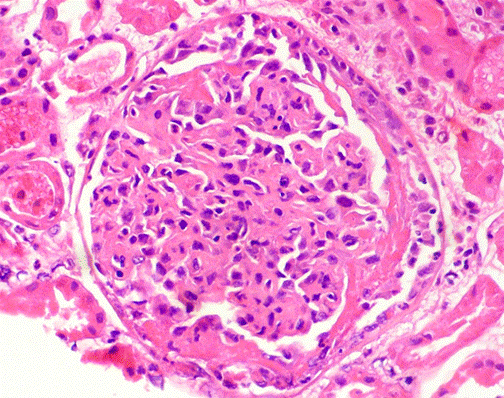

Se realizó diagnóstico de síndrome nefrítico agudo de etiología a determinar y en el seguimiento se identificó deterioro progresivo y severo de la función renal, por lo que se hizo impresión diagnóstica de glomerulonefritis rápidamente progresiva y se decidió iniciar bolos endovenosos de esteroides por tres días consecutivos y realizar biopsia renal guiada por ecografía con estudio histológico que reportó glomerulonefritis con proliferación endocapilar y extracapilar con semilunas epiteliales (Figuras 1, 2, 3 y 4).

Las publicaciones de casos de patrones de glomerulonefritis con proliferación extracapilar secundarias a procesos infecciosos en el adulto son escasas. Sin embargo, existen registros en población pediátrica como el de Dewan et al.22, donde 19 de los 22 casos de glomerulonefritis con proliferación extracapilar estuvieron relacionados con depósitos de inmunocomplejos, predominantemente de etiología postinfecciosa. Adicionalmente, otros trabajos han mostrado resultados similares con una incidencia de alrededor del 12% de proliferación extracapilar relacionada con GNPI23,24.

La GNPI con proliferación extracapilar tiene un peor pronóstico con respecto a los patrones clásicos de presentación de la nefritis. Pero además, es de anotar que su pronóstico también depende del número de semilunas encontradas, su tipo histológico, el compromiso tubulointersticial y si hay acompañamiento clínico de proteinuria en rango nefrótico o compromiso severo de la función renal en el debut25.